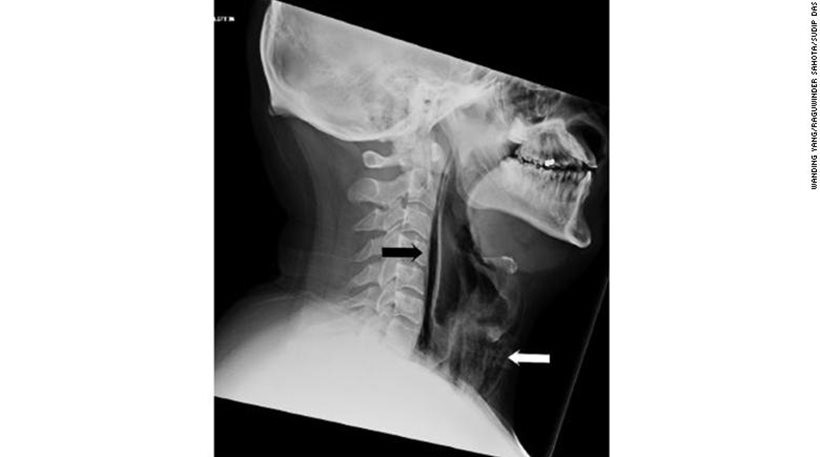

Ακτινογραφία αποκάλυψε ότι αέρας εξερχόταν από την τραχεία του προς τον μαλακό ιστό του μέσω της “ρωγμής” που είχε σχηματιστεί.

Όταν τον εξέτασαν οι γιατροί διαπίστωσαν ότι υπήρχε οίδημα στον λάρυγγα και γύρω από τον λαιμό του.